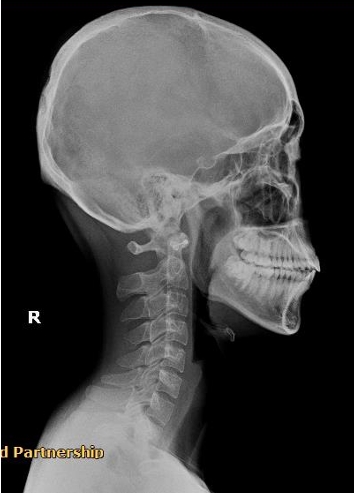

พนักงานออฟฟิศ (Case 3)

อาการ: ออฟฟิศซินโดรม / กระดูกคอตรง

"จากการนั่งทำงานหน้าคอมพิวเตอร์เป็นเวลานาน ทำให้กระดูกคอเสียความโค้ง หลังรับการฟื้นฟู สรีระคอดีขึ้น อาการปวดบ่าร้าวขึ้นศีรษะลดลงอย่างเห็นได้ชัด"

Before

After